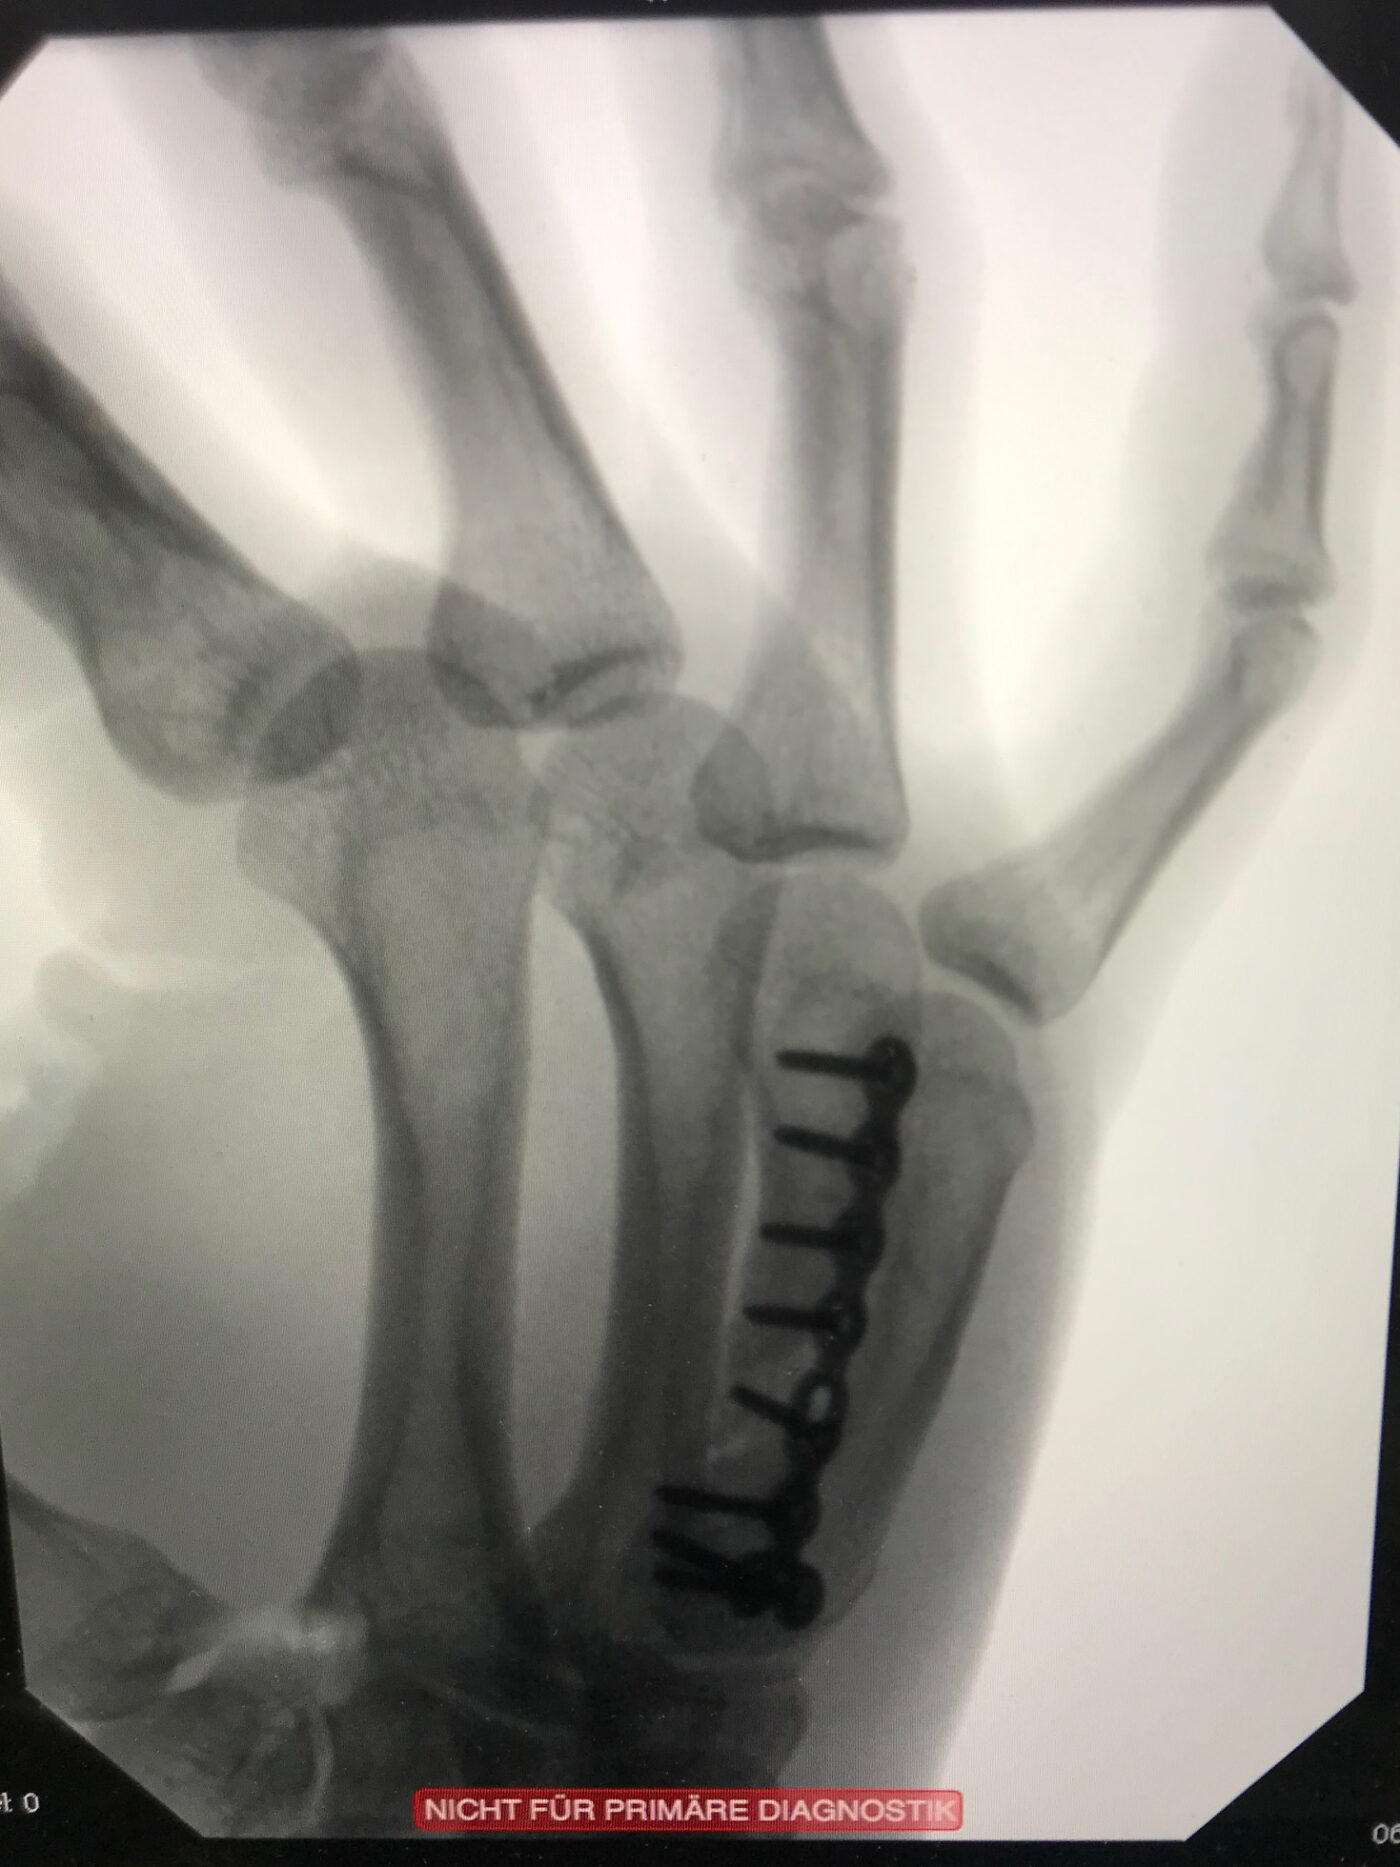

Nach Puckeinschlag mit 160 km/h: die Hand zum vierten Mal gebrochen.

Nach Knochentransplantation von der Speiche: der Mittelknochen ist repariert.

Der Kanadier erlitt zum vierten Mal einen Knochenbruch in seiner rechten Hand: Nach Zeigefinger- und kompliziertem Daumenbruch hielt ein weiterer Finger der enormen Wucht des Pucks nicht stand. «Aus ärztlicher Perspektive hätte man die Operation sofort durchführen müssen. Durch das Warten wurden die Finger immer krummer und kürzer», erinnert sich Dr. Jürgensen.

Doch solche Bedenken und Schmerzen halten Eishockeyspieler nicht vom Eis fern: Ein bisschen «Tape» muss reichen. Mit den Worten «As long as you win», liess der Handchirurg den Spieler wohl oder übel gewähren. Erst eine Woche nachdem der SCB den Sieg geholt hatte und die Siegesfeiern vorbei waren, wurde endlich operiert. In einer aufwändigen Rekonstruktion entnahm Dr. Kay Jürgensen Knochen von der Speiche und transplantierte diese an den Mittelknochen – wo vorher ein Loch war. «Den Finger habe ich wieder auf die richtige Länge gebracht und richtig eingestellt».